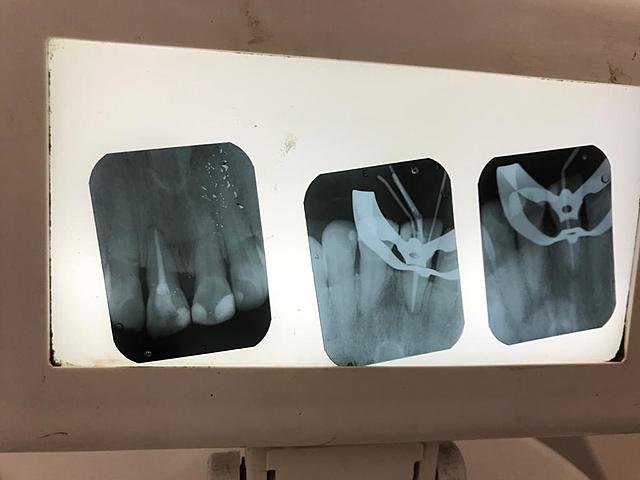

Se realizó inicio de tratamiento endodóntico en OD 1.1 se tomo cabometria, se instrumento hasta lima # 50, se realizó el retroceso con limas # 60, 70 y 80, se coloco hidróxido de calcio en el conducto y se obturó de manera provisional con CAVIT

Se retiró el material de curación, se colocó una gutapercha numero 50 y tres accesorias FM con SIELAPEX y se obturó de manera provisional con CAVIT

Se refirió a paciente para realización de endodoncia en el OD 1.6. se realizó el inicio hasta aqui va el tratamiento

Pendiente realizar final de endodoncia del OD 1.6